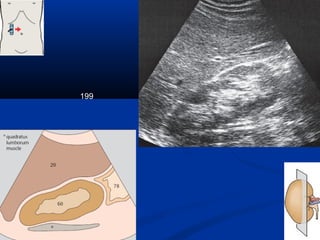

Kyõ thuaät : caùc maët caétKyõ thuaät : caùc maët caét

199